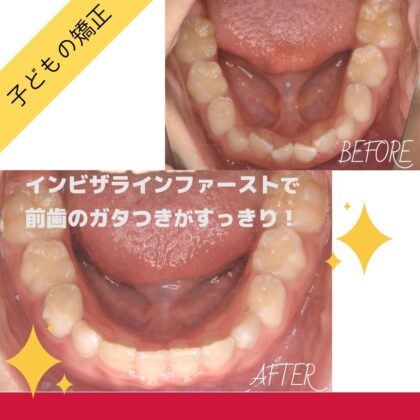

2025.08.04

年齢 10歳 主訴 前歯のガタガタが気になる...